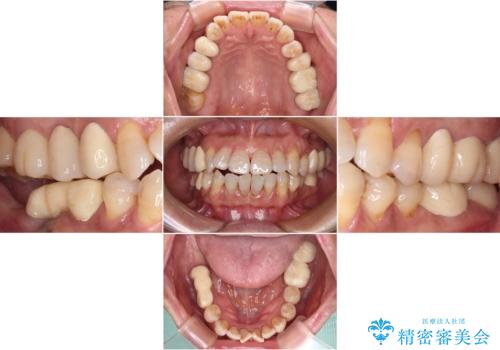

- 治療をおこなって以来、クラウン周りの歯肉から出血が続くとのことで来院された患者様です。

診察を行ったところ、クラウンと歯の境目が不適合で汚れが溜まりやすく、炎症を起こしている状態でした。

治療を終えたばかりですが、出血を改善するためには作り直しが必要と判断し、オールセラミッククラウンにて補綴治療することとしました。

他にも、咬合時に痛みを感じる歯や、欠損により咬みにくい奥歯などをインプラントを用いて治療を行うこととしました。

仮歯に置き換えた時点で歯肉からの出血は収まり、不快感が改善されました。

右下は、残存歯の状態があまり良くなかったため、今後抜歯となったことを想定して、最後臼歯のインプラントを決定しました。